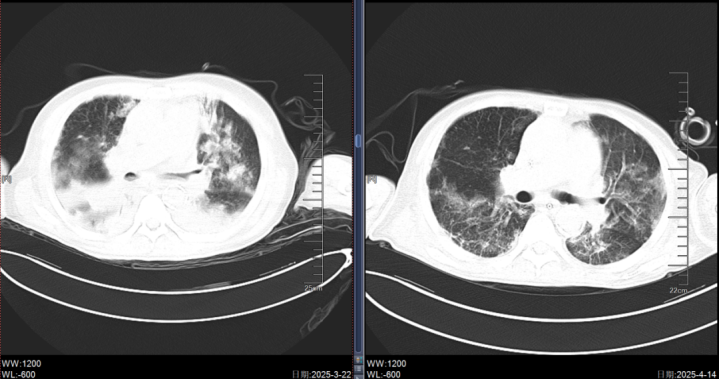

虽经积极抗病毒、抗感染治疗,患者病情仍急剧恶化,很快出现神志转差、血氧饱和度急剧下降等症状,诊断为重症肺炎合并呼吸衰竭,紧急转入ICU监护治疗。

ECMO启动后,医护团队24小时全程守护,开云密切监测患者的生命体征、凝血功能、感染指标等,根据病情变化及时调整治疗方案。随着治疗的逐步推进,患者的感染得到有效控制,呼吸功能逐渐恢复。

在ECMO支持11天后,成功撤机;又经7天精心治疗与呼吸康复,张先生神志转清,顺利拔除气管插管,转回普通病房继续治疗,最终康复出院。